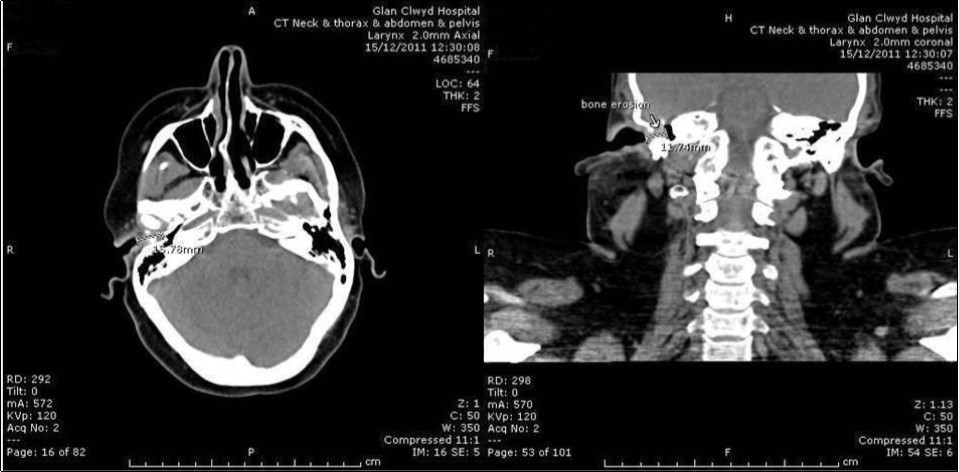

She had CT and MRI of her head. The CT showed occlusion of right external auditory canal with soft tissue mass with bone destruction superiorly. The soft tissue pushed the tympanic membrane into the middle ear which was itself pneumatised and free of the disease (Figure 3). The MRI detected intracranial extension into posterior fossa (Figure 4). She had also CT scan of neck, thorax, abdomen and pelvis for staging that didn’t show further disease.

Figure 3.Coronal CT head showing soft tissue occluding right EAC; bony destruction of the roof.